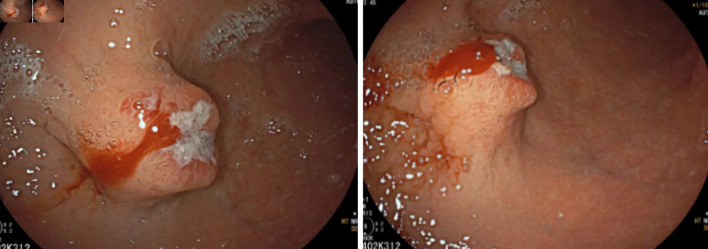

Gastric schwannomas and gastrointestinal stromal tumors (GISTs) are two types of mesenchymal tumors, which represent a group of rare tumors of the gastrointestinal tract. The differential diagnosis between these two tumors is difficult given their very similar appearance and clinical features. The authors present a case of a 63-year-old man with melena and epigastric pain. An upper digestive endoscopy was performed, revealing an ulcerated gastric subepithelial lesion suspected to be a GIST. Further imaging with a computed tomography (CT) scan revealed a well-defined hypodense solid nodular mass, with homogeneous enhancement, measuring 22 × 18 mm, on the anterior wall of the transition between the body and gastric antrum, situated within the submucosal layer. The patient subsequently underwent a laparoscopic atypical gastrectomy, which proceeded without complications. The pathological examination of the excised lesion confirmed it to be a gastric schwannoma, with complete excision. This case report illustrates a rare cause of gastrointestinal bleeding, that requires immediate action, and en bloc resection is usually curative. Given the excellent prognosis after complete resection, a correct diagnosis is essential.